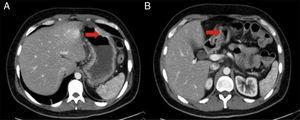

A la exploración física con diaforesis, taquicardia, febrícula y presión arterial sin alteraciones. Dolor epigástrico a la palpación superficial sin organomegalias. Las pruebas de laboratorio con leucocitos de 23,6×103μl, neutrófilos 21×103μl, linfocitos 0,9%, Hb 12,7g/dl, VCM 78,5fl, proteína C reactiva 21,61mg/dl; resto de pruebas del laboratorio dentro de los parámetros normales. Se le realiza tomografía axial computarizada (TAC) de abdomen (fig. 1) la cual reporta: «Importante engrosamiento en la pared gástrica y duodenal de etiología por determinar. Ganglios mesentéricos y retroperitoneales de morfología reactiva y atrofia pancreática».